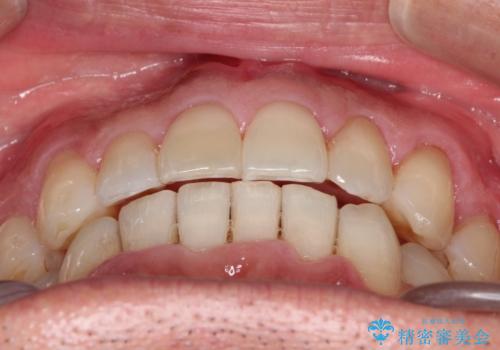

インビザライン invisalign ガタつきを治すマウスピース矯正

- 非抜歯・上顎臼歯遠心移動によるマウスピース矯正を計画した。

ガタつきを取り除くだけであれば非常に簡潔であるマウスピース矯正ですが、奥歯の位置関係の是正や、垂直的な歯の位置のコントロールなどが計画に含まれる場合、治療が難しくなってきます。